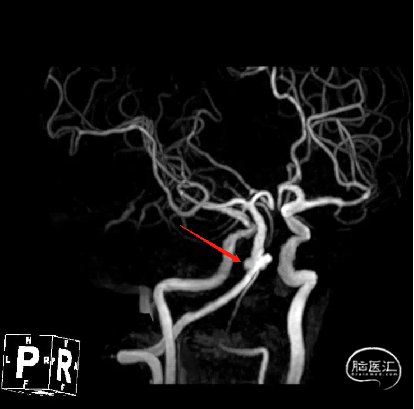

术前MRI+MRA示:脑桥急性梗死,动脉瘤位于基底动脉近端,左侧椎动脉优势。

通过3D工作位测量出基底动脉瘤瘤颈最宽处:6.5mm;载瘤动脉尺寸:近端直径3.7mm,远端直径4.2mm。

基底动脉不规则动脉瘤,瘤颈最宽处6.5mm。

动脉瘤位于基底动脉近端,左椎动脉优势,经股入路路径迂曲,经左桡入路相对较易。